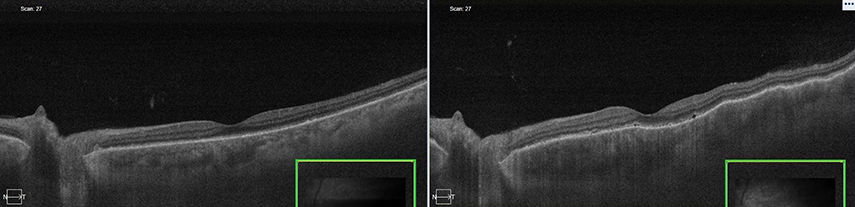

再燃前後のOCT画像(左がプレドニン12.5mg内服時、右がプレドニン10mg内服時)

出典

img

1: 著者提供